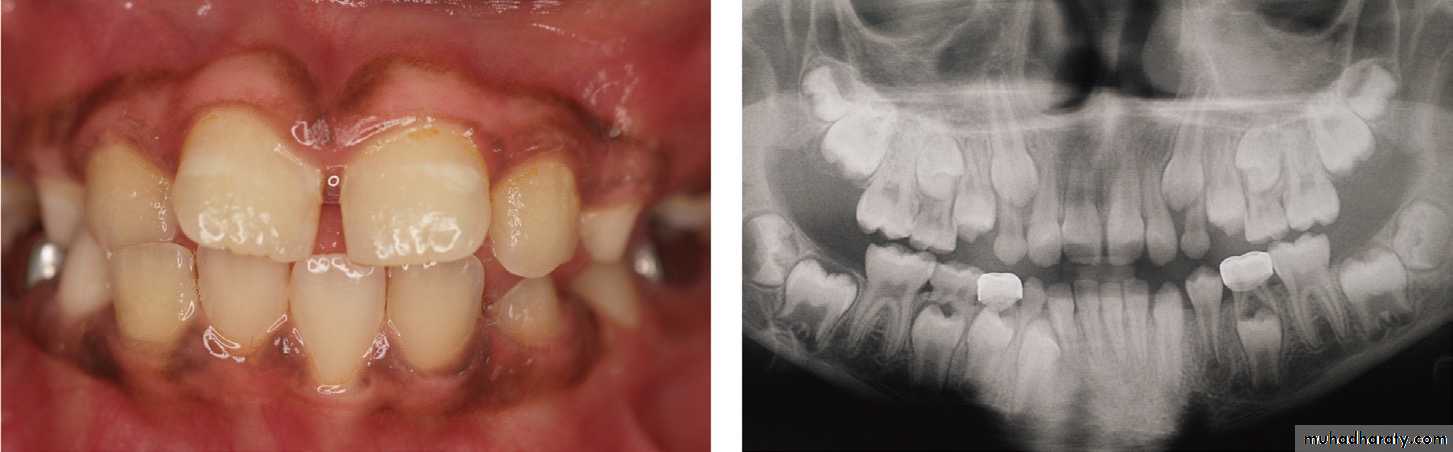

Usually, the permanent teeth when erupt ,they are located at the palatal or lingual aspect of the deciduous incisors, causing their resorption during eruption, but sometimes, the permanent teeth could be deflected from the roots of incisors; therefore, this process will not happen in the normal way, and the permanent erupt ,while the deciduous is stay in its space.

The permanent central incisors and the lateral incisors erupt palatal to the deciduous incisors in the upper arch, and lingual to the deciduous incisors in the lower arch, and in their development (eruption), they should be guided into a downward and forward direction to contact the roots of the deciduous incisors causing their resorption.Additionally the permanent incisors located in their crypts in a (zigzag) fashion, and the lateral usually trapped by the central incisors.

Anyhow, if the incisors deflected from this path of eruption, ⇒ they will erupt lingual and/or palatal to the deciduous incisors and this will lead to “anterior cross bite”, but if there is normal path of eruption, they will erupt in a normal way. Since the lateral incisor situated lingual or palatal to the central incisor, therefore they may be influenced by: malocclusion more than the centrals; because they erupt later and if there is no available space in the dental arch ⇒the centrals will occupy the available space, and the remnant of the space may be not enough for the eruption of the lateral incisors. Therefore, they will be erupted in a rotated or cross bite condition. In the normal way: the lateral escapes from the central incisors at the time the centrals begun to erupt.